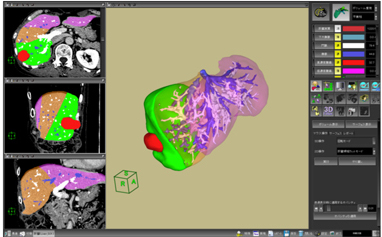

肝臓には動脈,門脈,静脈などの血管系が存在し,複雑に走行しています。その内部の血管走行をあらかじめ知っておくことは,肝切除術の術前情報として非常に重要です。肝臓解析ソフトウェアでは,新しいレンダリング技術を採り入れることにより,肝臓内部の血管走行を明瞭に表現することを可能にしました(図5)。さらに,血管支配領域をシミュレートした際の境界面にMPRを表示させることも可能です(図6)。それぞれの血管の位置関係や距離,腫瘍付近の血管の詳細情報,および対象物の肝臓表面からの位置関係などを明瞭に表現することができます。

![]() 図5 肝臓解析ソフトウェア 新しいレンダリング法を用いることで肝臓内の血管走行を明確に表示します。 |